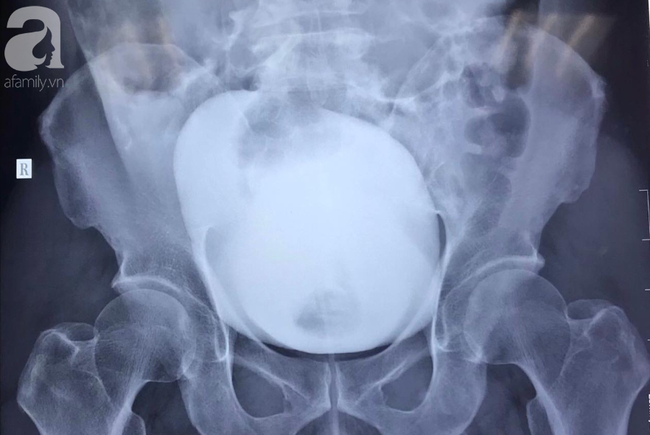

| Ảnh chụp X-quang cho thấy bàng quang bệnh nhân bị vỡ (có vùng đọng màu trắng ở giữa). |

Kết quả siêu âm bụng, CT bụng cản quang khẩn ghi nhận vỡ bàng quang trong phúc mạc.

Ca mổ cấp cứu được tiến hành trong đêm. Quá trình phẫu thuật, các bác sĩ xác định bệnh nhân vỡ bàng quang 7cm, nhiều máu trong ổ bụng.